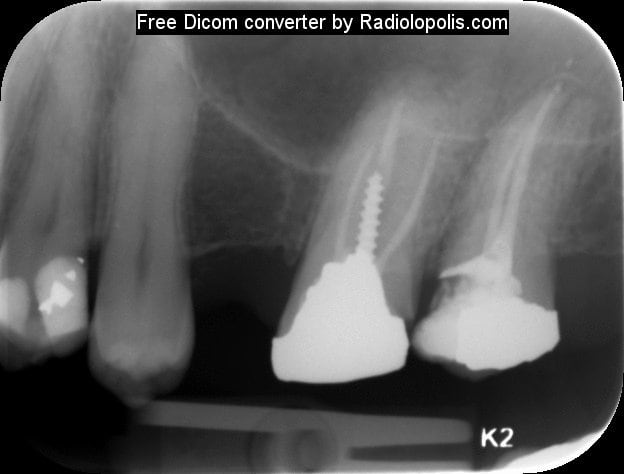

Comme promis voilà les radios .... Pas fier je suis.

Radiolopolis 1 pqzmoo - Eugenol

Radiolopolis 2 lnls6d - Eugenol

Radiolopolis mtbhfu - Eugenol

pfffffffffffff !!! franchement ce ne sera pas tres difficile pour toi de retirer cet instrument, tu prends une lime K 15 ou 10 et tu tentes de passer à coté tout en la plaquant contre l'instrument au moment du retrait (Ne force pas ta lime sinon deuxieme fracture!!!). tu irrigues beaucoup (avec de l'EDTA c'est encore mieux)jusqu'au moment où tu sentiras ton instrument se libérer.

Le RTE est possible mais difficile!

Autrement après retouche cavité d'accès+digue et effectivement utilisations de la techique by pass+éventuellement utilisation des kits genre Komet rescue pour tenter d'enlever le NITI+ultrasons+utilisations des loupes ou mieux microscope opératoire.Il y a un risque de faire un faux canal avec le bi pass.Je confirme ,il faut au moins une heure trente pour finir l'endo ,mais c'est certainement plus tranquille pour un endo exclusif.